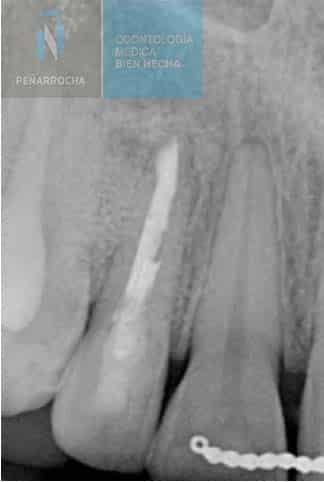

X-ray signs of a failed root canal treatment

One of the most reliable diagnostic tools for detecting root canal failure is dental radiography. With X-rays, the specialist can carefully examine the inside of the tooth and root canals to determine whether the treatment has been successful or if signs of failure are present.

Some of the most common radiographic signs of a failed root canal treatment include:

- Unfilled canals: an X-ray may reveal empty spaces along or at the end of the root canal that were not properly sealed. These gaps provide an entry point for bacteria, increasing the risk of infection and reinfection.

- Overfilling: when the filling material extends beyond the root apex, it can irritate the surrounding periapical tissues. On the radiograph, this appears as a white extension beyond the tip of the root.

- Dark areas around the root: dark or radiolucent zones in the bone surrounding the root are often a sign of infection or periapical lesions that compromise the bone structure.

- Periapical lesions: visible as darker or radiolucent areas around the tooth apex, periapical lesions indicate the presence of persistent inflammation or an active infection.

- Untreated canals: sometimes additional canals are missed during treatment. On an X-ray, they appear as radiolucent areas since they were not cleaned, shaped, or filled. Their presence can cause ongoing infection and treatment failure.

- Root fractures: although difficult to detect, root fractures may appear as fine, dark lines along the root. They can also cause irregular changes in the surrounding bone pattern, suggesting structural compromise.

In some cases, X-rays may show a radiolucent lesion around the apex of a tooth, even when the root canal appears to have been performed correctly. This suggests that, despite proper technique, the treatment has ultimately failed. A follow-up radiograph after apical surgery can often confirm the healing of the affected area.

In any situation, it is essential that an endodontist or oral surgeon evaluates the radiograph to accurately determine the condition of the tooth and whether additional treatment is required.